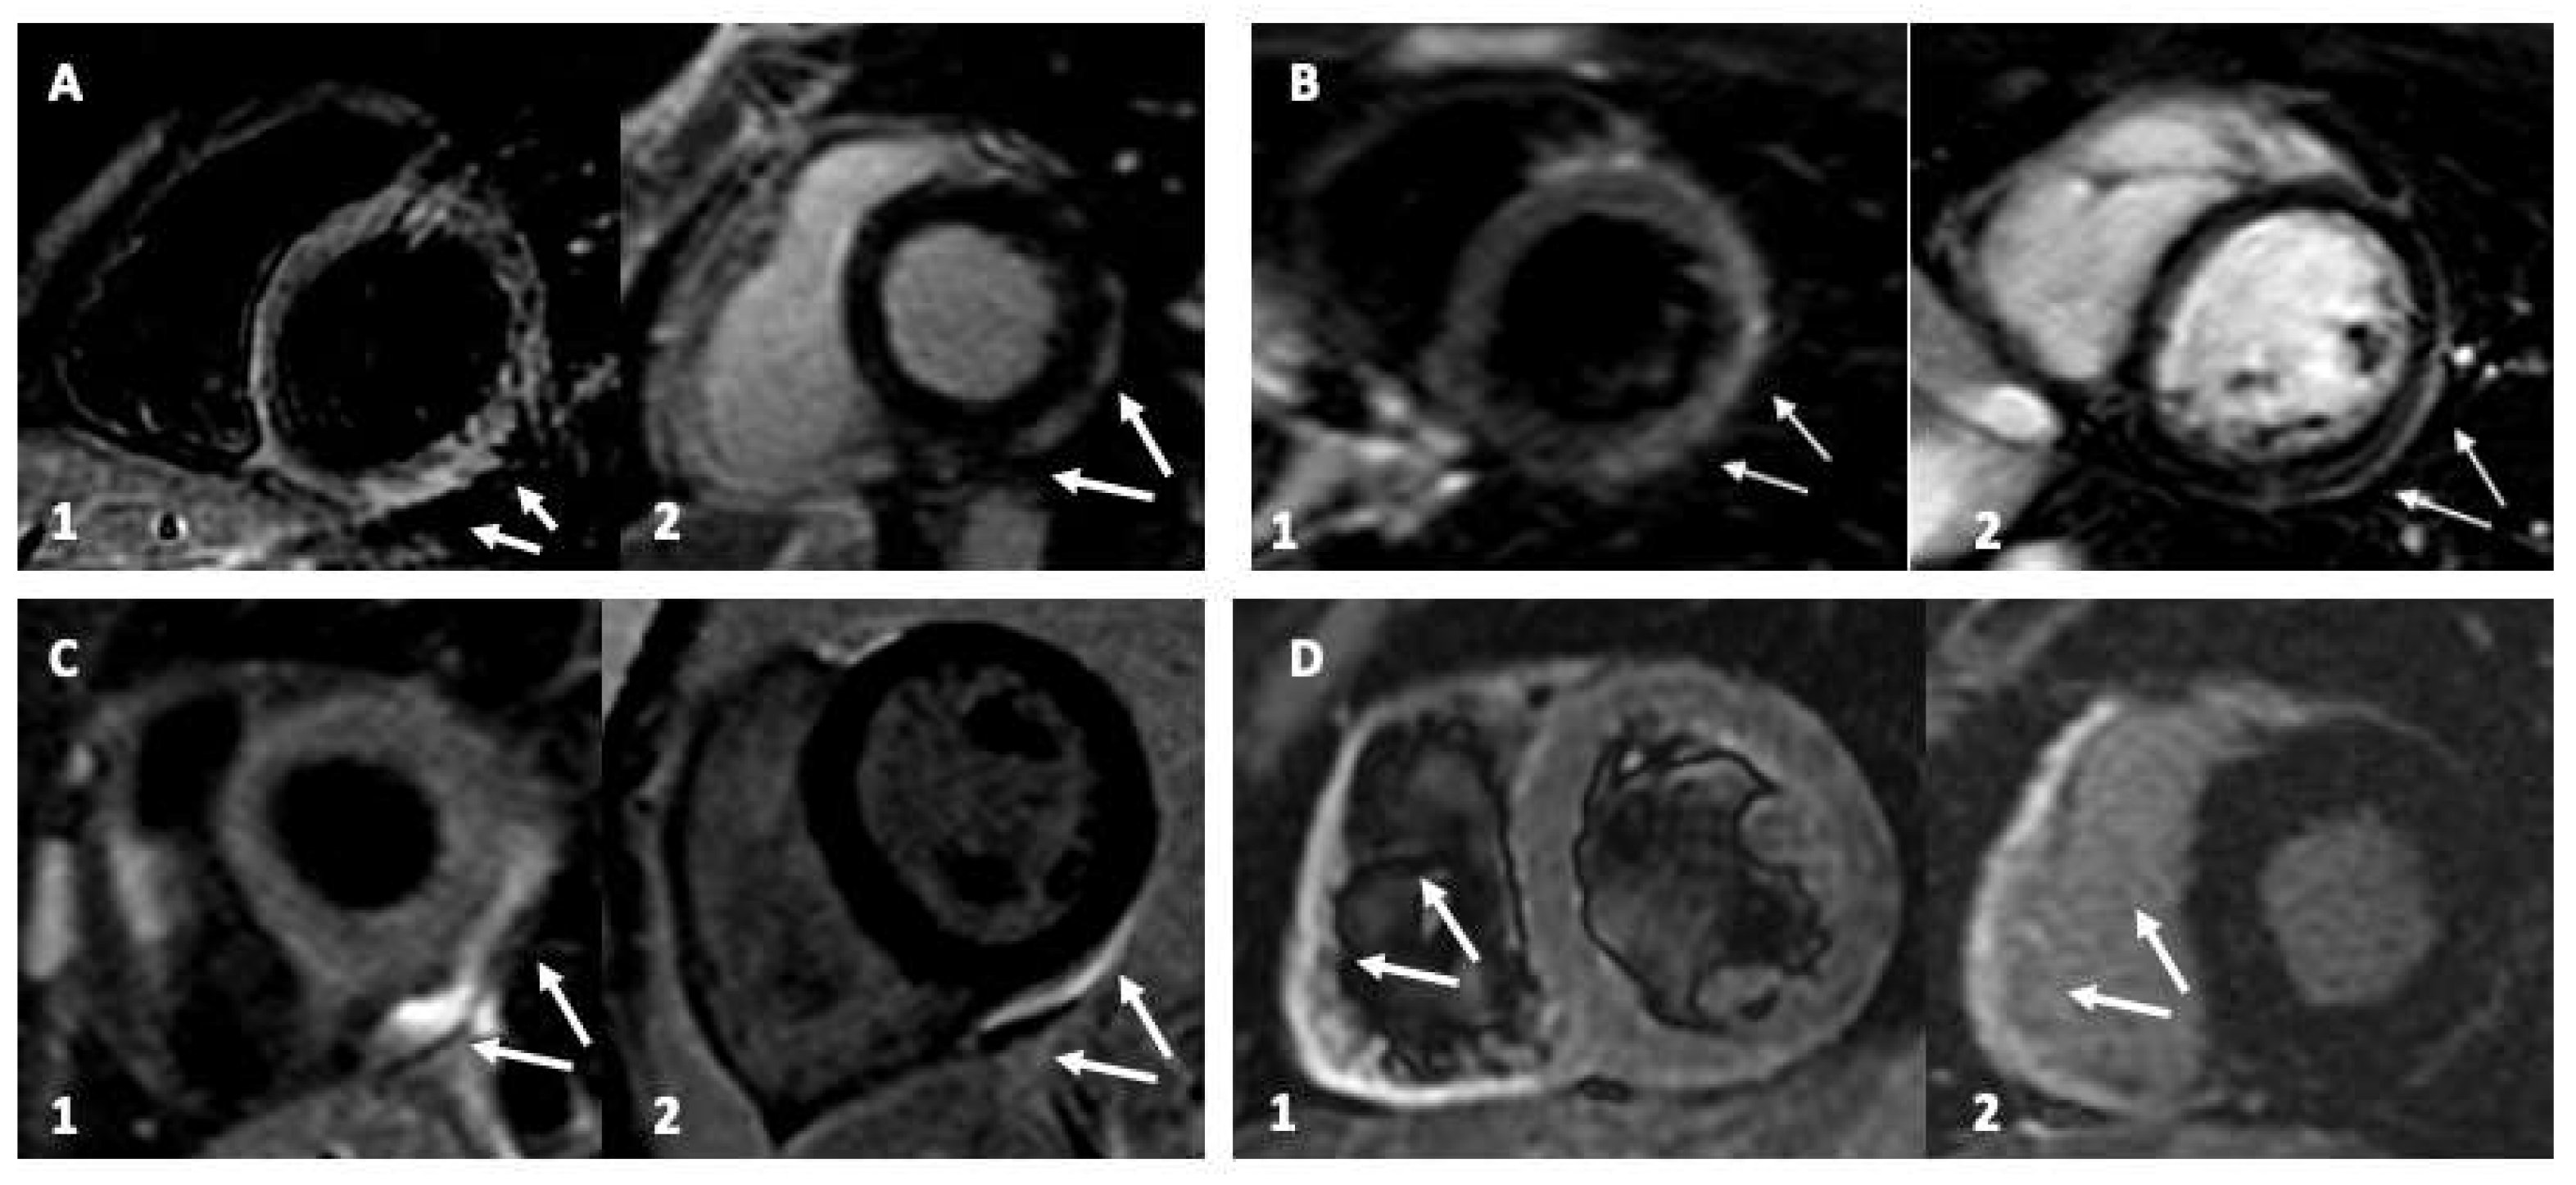

All the pertinent CMR findings are summarized and presented in Table 2 according to participants. Myocarditis was prevalent in males (65% (n = 4/6)). It was characterized by myocardial edema (T2w hyperenhancement) and LGE in the lateral wall of the left ventricle (LV). Only one patient showed an isolated right ventricular (RV) involvement, while the females presented prevalently with myopericarditis (30% (n = 2/6) (Figure 1). All patients in our series demonstrated preserved LV ejection fraction and remained clinically stable during a relatively short in-hospital stay.

Figure 1.

Cardiac magnetic resonance (CMR) imaging of young patients with vaccine-related myocardial involvement. Panel (A,B): Inferolateral myocardial involvement with edema and late gadolinium enhancement (LGE), with a subepicardial and pericardial distribution typical of myocarditis. Panel (C): Only pericardial involvement. Panel (D): isolated right ventricle involvement. Sub-Panel 1, triple IR (Triple-IR) FSE T2-weighted images for myocardial edema detection. Sub-Panel 2, LGE images.